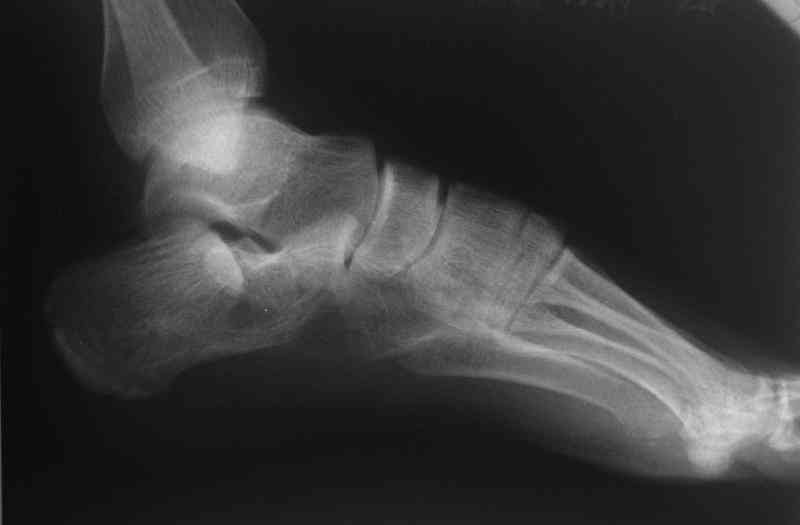

Re: Перелом пяточной кости

Открытый и закрытый способы лечения.